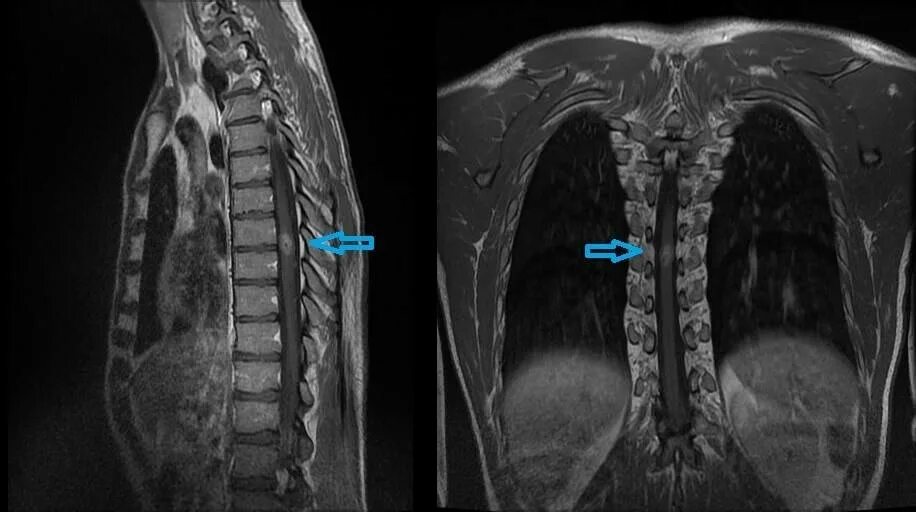

Киста в грудном отделе позвоночника